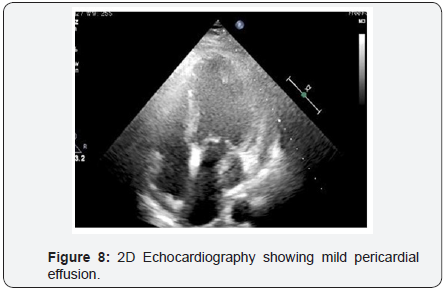

To decrease extravasation time during autologous blood embolisation, the left common femoral artery was accessed with a 6Fr sheath and a 6Fr EBU 3 guide catheter was advanced and placed adjacent to the 6Fr guide catheter at the LM ostium (Figure 4). This sequence of events was performed in approximately 4min and prevented the development of tamponade. A sion blue wire was then passed into the distal LCX with transient balloon deflation to allow wire passage. Autologous clotted blood injected through the aspiration thrombectomy (Pronto LP, Vascular Solutions, Minneapolis, MN) catheter was used to embolise the leaking vessel. The balloon was kept inflated during injection of clotted blood to prevent back leak. The LCX artery occluded instantaneously at proximal level with immediate stoppage of the leak into the pericardium .There was an excellent final result (Figure 5) and the absence of extravasation was confirmed in a repeat angiography (Figure 6). RCA (right coronary artery) angiogram was also taken (Figure 7) which did not reveal any leak from the collateral supply to the occluded LCX. The ECG showed Q waves in I, AVL and troponin values were positive. The following morning, the echocardiogram showed mild pericardial and pleural effusion (Figure 8) and the patient was discharged at 72hrs with a subsequent uneventful course.